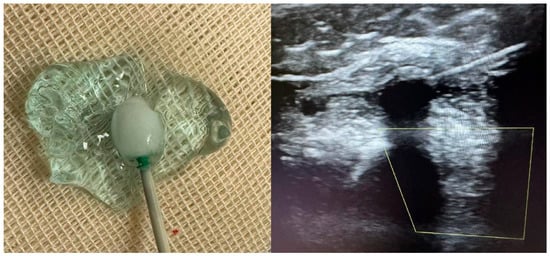

2. Procedural Technique